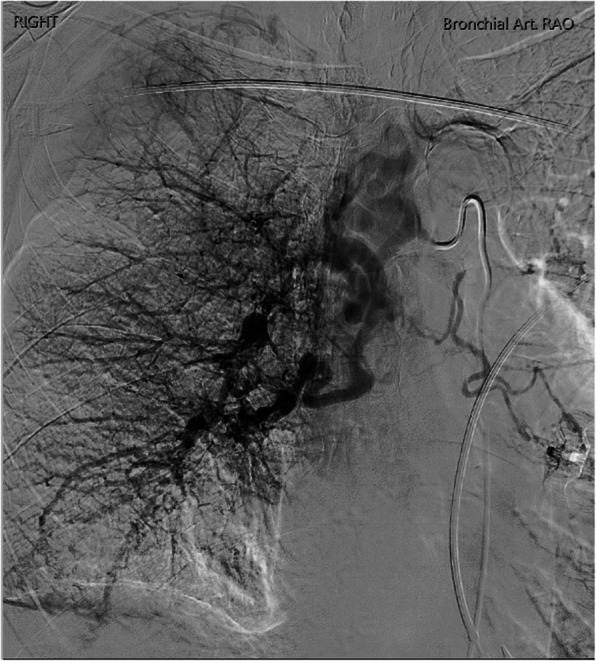

{"title":"肺动脉近端中断伴全身支气管/肋间动脉瘤形成:1例报告。","authors":"Runlin Yang, Robert Ng, Albert Goh, Richard Pow","doi":"10.1186/s42155-025-00519-0","DOIUrl":null,"url":null,"abstract":"<p><p>Proximal Interruption of the Pulmonary Artery (PIPA) is a rare congenital condition with an incidence of 1 in 200,000-300,000 individuals. We report the case of a 67-year-old woman with PIPA who presented with massive haemoptysis. Imaging revealed a small calibre right main pulmonary artery, absence of upper/middle lobe pulmonary arteries, and tortuous right systemic collateral arteries. A multidisciplinary meeting favoured bronchial artery embolisation over right pneumonectomy, due to the bleeding risk associated with extensive transpleural systemic collateral arteries. The patient underwent two staged bronchial artery embolisation and remained free of haemoptysis at the most recent 13-month follow-up. This case highlights the potential for bronchial artery embolisation to serve as a first-line treatment in managing PIPA, as a less invasive alternative to surgery.</p>","PeriodicalId":52351,"journal":{"name":"CVIR Endovascular","volume":"8 1","pages":"60"},"PeriodicalIF":1.5000,"publicationDate":"2025-08-01","publicationTypes":"Journal Article","fieldsOfStudy":null,"isOpenAccess":false,"openAccessPdf":"https://www.ncbi.nlm.nih.gov/pmc/articles/PMC12316662/pdf/","citationCount":"0","resultStr":"{\"title\":\"Proximal interruption of the pulmonary artery with systemic bronchial/intercostal aneurysm formation: a case report.\",\"authors\":\"Runlin Yang, Robert Ng, Albert Goh, Richard Pow\",\"doi\":\"10.1186/s42155-025-00519-0\",\"DOIUrl\":null,\"url\":null,\"abstract\":\"<p><p>Proximal Interruption of the Pulmonary Artery (PIPA) is a rare congenital condition with an incidence of 1 in 200,000-300,000 individuals. We report the case of a 67-year-old woman with PIPA who presented with massive haemoptysis. Imaging revealed a small calibre right main pulmonary artery, absence of upper/middle lobe pulmonary arteries, and tortuous right systemic collateral arteries. A multidisciplinary meeting favoured bronchial artery embolisation over right pneumonectomy, due to the bleeding risk associated with extensive transpleural systemic collateral arteries. The patient underwent two staged bronchial artery embolisation and remained free of haemoptysis at the most recent 13-month follow-up. This case highlights the potential for bronchial artery embolisation to serve as a first-line treatment in managing PIPA, as a less invasive alternative to surgery.</p>\",\"PeriodicalId\":52351,\"journal\":{\"name\":\"CVIR Endovascular\",\"volume\":\"8 1\",\"pages\":\"60\"},\"PeriodicalIF\":1.5000,\"publicationDate\":\"2025-08-01\",\"publicationTypes\":\"Journal Article\",\"fieldsOfStudy\":null,\"isOpenAccess\":false,\"openAccessPdf\":\"https://www.ncbi.nlm.nih.gov/pmc/articles/PMC12316662/pdf/\",\"citationCount\":\"0\",\"resultStr\":null,\"platform\":\"Semanticscholar\",\"paperid\":null,\"PeriodicalName\":\"CVIR Endovascular\",\"FirstCategoryId\":\"1085\",\"ListUrlMain\":\"https://doi.org/10.1186/s42155-025-00519-0\",\"RegionNum\":0,\"RegionCategory\":null,\"ArticlePicture\":[],\"TitleCN\":null,\"AbstractTextCN\":null,\"PMCID\":null,\"EPubDate\":\"\",\"PubModel\":\"\",\"JCR\":\"Q3\",\"JCRName\":\"CARDIAC & CARDIOVASCULAR SYSTEMS\",\"Score\":null,\"Total\":0}","platform":"Semanticscholar","paperid":null,"PeriodicalName":"CVIR Endovascular","FirstCategoryId":"1085","ListUrlMain":"https://doi.org/10.1186/s42155-025-00519-0","RegionNum":0,"RegionCategory":null,"ArticlePicture":[],"TitleCN":null,"AbstractTextCN":null,"PMCID":null,"EPubDate":"","PubModel":"","JCR":"Q3","JCRName":"CARDIAC & CARDIOVASCULAR SYSTEMS","Score":null,"Total":0}

近端肺动脉中断(PIPA)是一种罕见的先天性疾病,发病率为20 -30万分之一。我们报告的情况下,67岁的妇女PIPA谁提出了大量咯血。影像学显示右肺主干小口径,肺上/中叶动脉缺失,右全身侧支动脉迂曲。一个多学科会议倾向于支气管动脉栓塞而不是右侧肺切除术,因为出血风险与广泛的经胸膜全身侧支动脉相关。患者接受了两次分阶段支气管动脉栓塞,在最近13个月的随访中仍无咯血。该病例强调了支气管动脉栓塞作为治疗PIPA的一线治疗方法的潜力,作为一种侵入性较小的手术替代方法。

Proximal Interruption of the Pulmonary Artery (PIPA) is a rare congenital condition with an incidence of 1 in 200,000-300,000 individuals. We report the case of a 67-year-old woman with PIPA who presented with massive haemoptysis. Imaging revealed a small calibre right main pulmonary artery, absence of upper/middle lobe pulmonary arteries, and tortuous right systemic collateral arteries. A multidisciplinary meeting favoured bronchial artery embolisation over right pneumonectomy, due to the bleeding risk associated with extensive transpleural systemic collateral arteries. The patient underwent two staged bronchial artery embolisation and remained free of haemoptysis at the most recent 13-month follow-up. This case highlights the potential for bronchial artery embolisation to serve as a first-line treatment in managing PIPA, as a less invasive alternative to surgery.